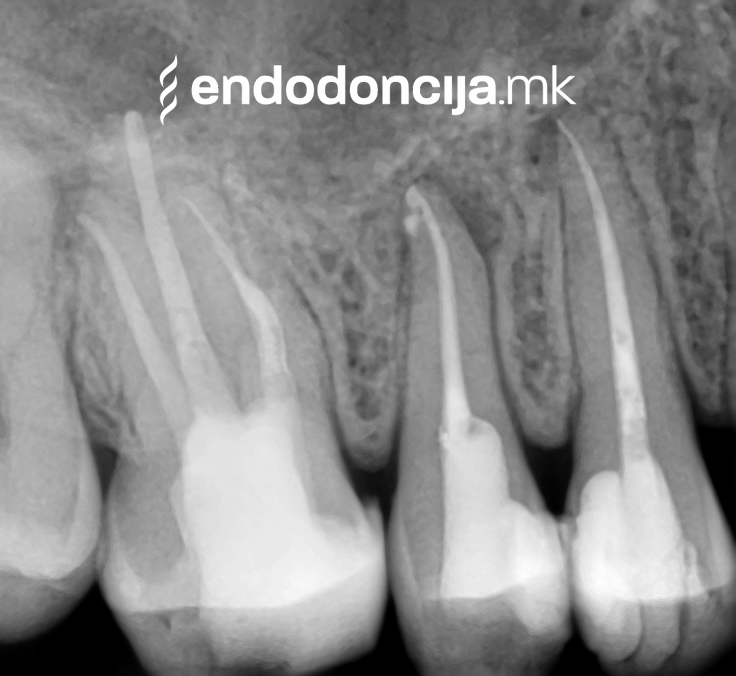

На специјализираниот оддел за ендодонција, нашите пациенти ги лекуваме на највисоко професионално и дијагностичко ниво. Опремени сме со најсовремени хируршки микроскопи, кои поддржуваат детален приказ и подготовка на коренот и нудат комплетно ново ниво на прецизност. Најновата ендодонтска опрема, инструментите и материјалите за полнење се во секојдневна употреба. На овој начин третманот станува пократок, дури и во комплицирани случаи, и се избегнува губење на забите.

За време на претходните третмани, забот не само што бил ослабен со механички третман на коренскиот канал, туку и со поставување и закотвување на забното колче. Кога се ревидира третманот со коренскиот канал, овие колчиња треба да се отстранат колку што е можно повнимателно за да се задржи важната забна супстанција.

Она што е импресивно е прецизноста на микроскопските третмани. Дури и кога каналите се потешко достапни, може да се лоцираат и исчистат така што релапсите се со помала веројатност. Спротивно на тоа, скриените канали често остануваат неоткриени во конвенционалниот третман на коренскиот канал и затоа не можат да се чистат. Бактериите можат да се размножуваат таму без пречки и да предизвикаат воспаленија. Ова често останува незабележано со години додека не се појави забоболка, а со тоа и компликации.